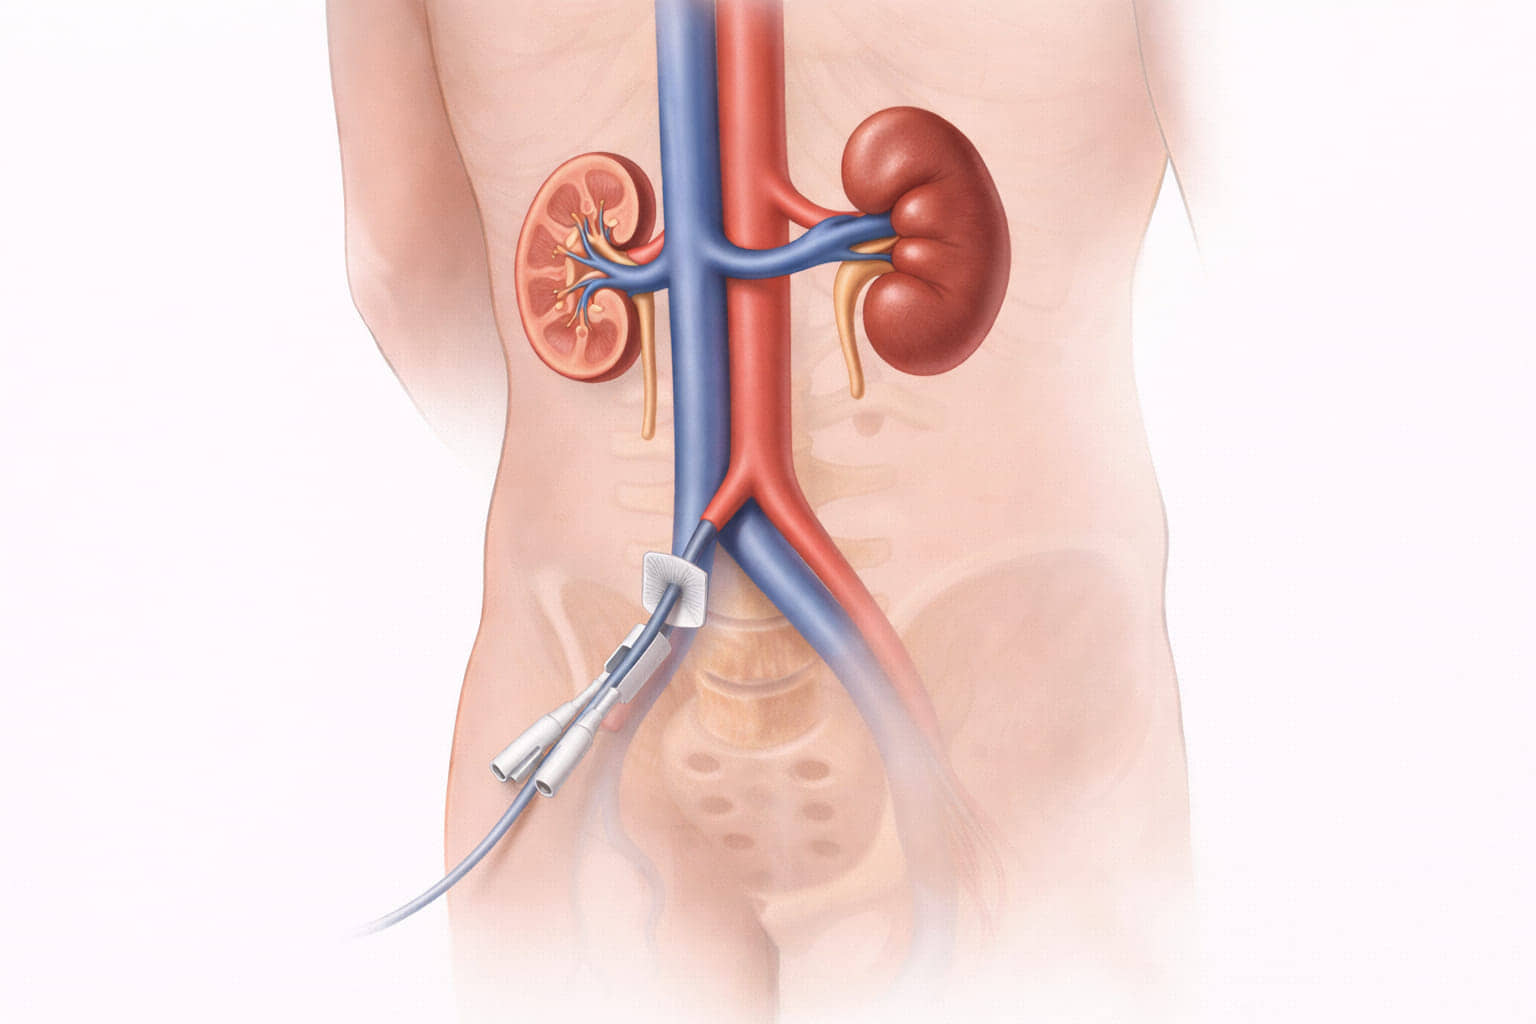

A Translumbar Venous Catheter provides a critical solution when traditional access points are exhausted. Instead of the neck or chest, a specialized catheter is placed directly into the Inferior Vena Cava (IVC) through the lower back, giving immediate, high-flow access for dialysis or essential infusions.

- Patient Positioning: The patient lies on their stomach or side.

- Imaging Guidance: Using real-time Fluoroscopy (X-ray) and sometimes CT guidance, Dr. Ram identifies the Inferior Vena Cava (IVC) sitting just in front of the spine.

- Percutaneous Access: A needle is precisely guided through the skin of the lower back and into the IVC.

- Catheter Placement: A long-term, tunneled catheter is threaded into the vein. The “tunneling” helps prevent infection and ensures the catheter stays securely in place.

5. Immediate Function: Once placed, the catheter provides high-flow access immediately, allowing dialysis or life-saving infusions to proceed without delay.

- High Flow Rates: The IVC is a large vessel, allowing for the high blood-flow rates required for efficient dialysis.

Because the IVC is near the spine and major arteries, there is a small risk of bleeding (hematoma). However, because Dr. Ram uses high-definition imaging guidance, these risks are minimized.